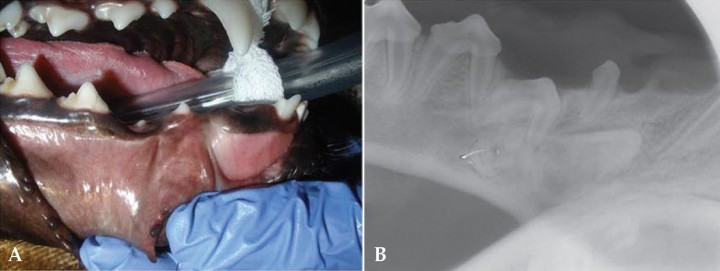

Linguoversión de los caninos mandibulares

Al igual que en el caso anterior se trata de una maloclusión de clase 1[ Wiggs RB, Lobprise HB. Veterinary Dentistry, Principles and Practice. Lippincott-Raven, Philadelphia. 1997; 130; 440-444; 472-474 . , Angle EH. Treatment of malocclusion of the teeth and fractures of the maxillae. Angle’s System. S White Manufacturing Co, Philadelphia. 1900; 34-44; 192-232. ] existiendo una mayor predisposición en determinadas razas dolicocéfalas y en el Caniche.[ Brook AN. Pathology in the pediatric patient. En: Niemiec B: Small Animal Dental, Oral and Maxillofacial Disease. Manson Publishing. London 2010; 90-123. , Harvey CE, Emily PP. Small Animal Dentistry, Mosby, St.Louis. 1993. ] En este caso, los caninos mandibulares se desplazan lingualmente.[ Brook AN. Pathology in the pediatric patient. En: Niemiec B: Small Animal Dental, Oral and Maxillofacial Disease. Manson Publishing. London 2010; 90-123. , Shipp AD, Fahrenkrug P. Practicioner’s Guide to Veterinary Dentistry. Dr. Shipps Laboratories, Beverly Hills. 1992; 122-123. ] Se debe a causas diversas como traumatismos, quistes, neoplasias, persistencia de la dentadura decidua y malposicionamiento del primer molar o tercer incisivo mandibular, que pueden interferir con el patrón normal de erupción[ Brook AN. Pathology in the pediatric patient. En: Niemiec B: Small Animal Dental, Oral and Maxillofacial Disease. Manson Publishing. London 2010; 90-123. , Harvey CE, Emily PP. Small Animal Dentistry, Mosby, St.Louis. 1993. , Wiggs RB, Lobprise HB. Veterinary Dentistry, Principles and Practice. Lippincott-Raven, Philadelphia. 1997; 130; 440-444; 472-474 . , Niemic BA: Unerupted, supernumerary P1 causing lingual deviation of the lower left canine (304). Vet Dent Forum Proceed, New Orleans. 1998; 145. ] (Fig. 8). Se puede encontrar en la dentadura decidua y en la permanente.

<p>A. Linguoversión de los caninos mandibulares. El canino mandibular izquierdo ocluye lingual al canino maxilar izquierdo B. Nótese el defecto traumático en el paladar. (Imagen cedida por A. Castejón González. Copyright Dentistry and Oral Surgery Service. Penn Vet. University of Pennsylvania).</p>

A. Linguoversión de los caninos mandibulares. El canino mandibular izquierdo ocluye lingual al canino maxilar izquierdo B. Nótese el defecto traumático en el paladar. (Imagen cedida por A. Castejón González. Copyright Dentistry and Oral Surgery Service. Penn Vet. University of Pennsylvania).

Los pacientes, con frecuencia no muestran sintomatología clínica; sin embargo, puede encontrarse dolor oral y sangrado por la cavidad bucal.[ Brook AN. Pathology in the pediatric patient. En: Niemiec B: Small Animal Dental, Oral and Maxillofacial Disease. Manson Publishing. London 2010; 90-123. ] Además, se puede producir un trauma palatino severo, llegando incluso a originarse fístulas oronasales, daño periodontal y desgaste por atrición en el canino maxilar.[ Hale FA. Juvenile Veterinary Dentistry. Vet Clin North Am: Small Anim Pract. 2005; (35):789-817. [PubMed] , Shipp AD, Fahrenkrug P. Practicioner’s Guide to Veterinary Dentistry. Dr. Shipps Laboratories, Beverly Hills. 1992; 122-123. , De Simoi A: Complications of Mandibular Brachygnathism in a North African leopard. J Vet Dentistry, 2006; (23):89-95. [PubMed] ]

Existen numerosas opciones de tratamiento que se pueden dividir en dos; movimiento ortodóntico del diente o eliminación de la fuente del trauma.[ Brook AN. Pathology in the pediatric patient. En: Niemiec B: Small Animal Dental, Oral and Maxillofacial Disease. Manson Publishing. London 2010; 90-123. ] Si la maloclusión no es muy grave y se diagnostica pronto, se puede realizar la exéresis en cuña de la encía maxilar para guiar al diente a la posición correcta.[ Brook AN. Pathology in the pediatric patient. En: Niemiec B: Small Animal Dental, Oral and Maxillofacial Disease. Manson Publishing. London 2010; 90-123. , Wiggs RB, Lobprise HB. Veterinary Dentistry, Principles and Practice. Lippincott-Raven, Philadelphia. 1997; 130; 440-444; 472-474 . ] Además, podemos poner composite sobre la superficie coronal de los caninos mandibulares, para estimular el correcto movimiento dental.[ Brook AN. Pathology in the pediatric patient. En: Niemiec B: Small Animal Dental, Oral and Maxillofacial Disease. Manson Publishing. London 2010; 90-123. ] Otro método más barato, pero no por ello menos efectivo y que se ha realizado con éxito eligiendo bien los casos, es la terapia de la pelota de goma. Se trata del juego diario, mínimo tres veces al día, con una pelota de goma de tamaño, forma y composición adecuada para cada paciente, que fuerza al diente a su posición apropiada.[ Brook AN. Pathology in the pediatric patient. En: Niemiec B: Small Animal Dental, Oral and Maxillofacial Disease. Manson Publishing. London 2010; 90-123. , Verhaert L: A removable orthodontic device for the treatment of lingually displaced mandibular canine teeth in dogs. J Vet Dentistry 1999; (2): 69-75. [SAGE] , Verhaert L: Developmental oral and dental conditions. En: Tutt C, Deeprose J, Crossley D: BSAVA Manual of canine and feline dentistry. Gloucester, British Small Animal Veterinary Sssociation. 2007; 83-84. ]

Movimiento ortodóncico del diente

La terapia ortodóntica tiene excelentes resultados. El medio más común de lograr el movimiento deseado es a través de la realización de un plano inclinado.[ Brook AN. Pathology in the pediatric patient. En: Niemiec B: Small Animal Dental, Oral and Maxillofacial Disease. Manson Publishing. London 2010; 90-123. , Harvey CE, Emily PP. Small Animal Dentistry, Mosby, St.Louis. 1993. ] Se puede llevar a cabo mediante la aplicación de acrílicos dentales colocados directamente en la boca y remodelados hasta hacer un plano inclinado que redireccione los caninos inferiores hasta su posición normal con los movimientos de masticación, o con aparatos fabricados en el laboratorio dental y cementados a los caninos superiores (Fig. 9). También se pueden tratar estos casos con aparatos de placa partida y tornillo de expansión situados entre los dos caninos mandibulares.

<p>Movimiento ortodóncico del diente. Placa partida con tornillo de expansión para resolver la lingualización de los caninos mandibulares en un perro.</p>

Movimiento ortodóncico del diente. Placa partida con tornillo de expansión para resolver la lingualización de los caninos mandibulares en un perro.

Eliminación de la fuente del trauma

En este caso, el objetivo es que los caninos inferiores no contacten con la mucosa palatina y no la lesionen. Se puede conseguir de dos maneras, mediante un tallado coronal con pulpotomía vital,[ Brook AN. Pathology in the pediatric patient. En: Niemiec B: Small Animal Dental, Oral and Maxillofacial Disease. Manson Publishing. London 2010; 90-123. , Wiggs RB, Lobprise HB. Veterinary Dentistry, Principles and Practice. Lippincott-Raven, Philadelphia. 1997; 130; 440-444; 472-474 . ] o una exodoncia de los mismos.[ Brook AN. Pathology in the pediatric patient. En: Niemiec B: Small Animal Dental, Oral and Maxillofacial Disease. Manson Publishing. London 2010; 90-123. , Wiggs RB, Lobprise HB. Veterinary Dentistry, Principles and Practice. Lippincott-Raven, Philadelphia. 1997; 130; 440-444; 472-474 . ]